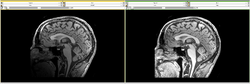

Image:Fiducial_registration_before.jpg|NEW: [[Modules:TransformFromFiducials-Documentation-3.6|Fiducial Registration]] (Casey Goodlett) | Image:Fiducial_registration_before.jpg|NEW: [[Modules:TransformFromFiducials-Documentation-3.6|Fiducial Registration]] (Casey Goodlett) | ||

NEW: Fiducial Registration (Casey Goodlett)